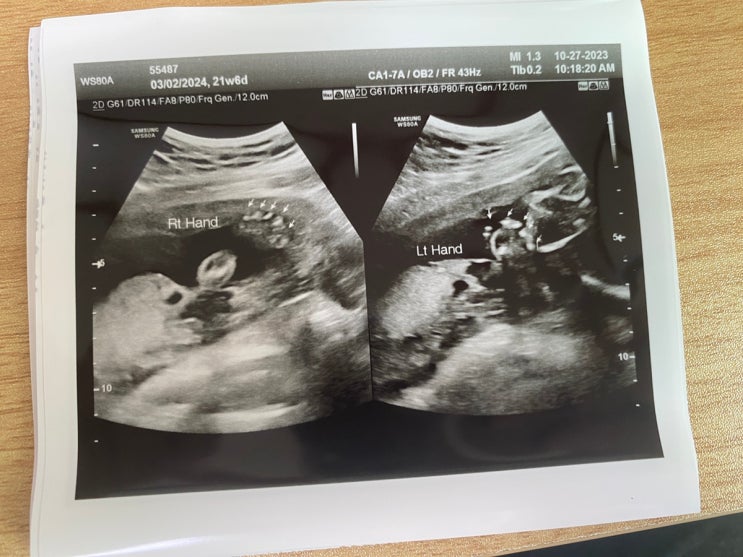

10월 27일 딸랑구 정밀 초음파(21주6일,6개월)

주원이 임신때는 나도 회사다니고 주말밖에 시간이없고.. 산부인과는 꼭 남편이랑 가야한다는 생각때문에 ...